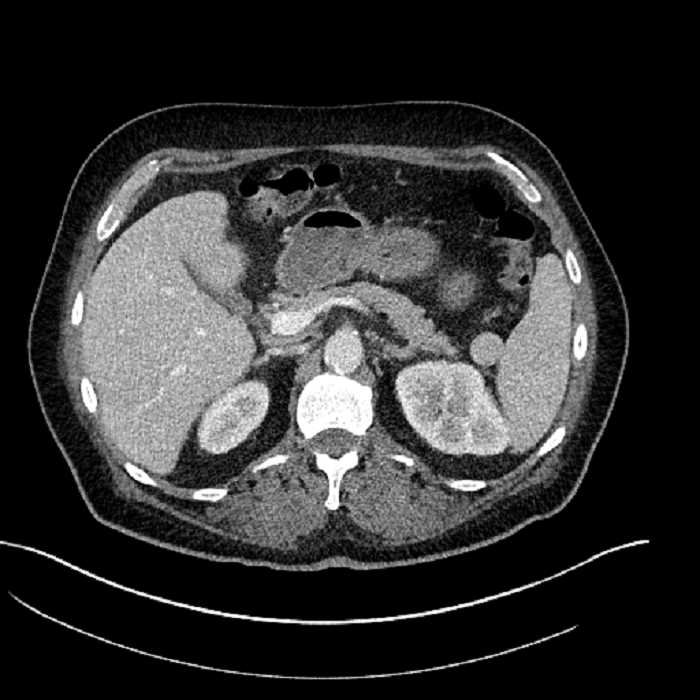

Age: 63

Sex: Male

Indication: Abdominal pain

• Large fluid density structure in hepatic segments 7 and 8 measuring 10 x 7 x 7 cm with internal septation and circumferential ill-defined low density compatible with edema

• Peripherally enhancing subcapsular collections along the anterior margin of the left hepatic lobe measuring 3 x 1 cm and 2 x 1 cm

• Clearly marginated fluid density structure in segment 7 and several other scattered tiny hypodensities, which likely represent cysts

• Hepatic abscess

Acute sigmoid diverticulitis complicated by a small contained perforation and a large abscess in the right hepatic lobe. Additional small subcapsular abscesses along the anterior margin of the left hepatic lobe.

• The classic CT imaging appearance is a double target sign with internal low density surrounded by an internal enhancing rim (capsule) and a low density external rim (edema)

• Abscesses may be unilocular or multilocular

• Gas is present in a minority of cases

Hepatic abscess showing the double target sign with low density internally surrounded by a thin inner enhancing rim (red arrow) and ill-defined outer low density rim (yellow arrow). Blue arrow indicates an internal septation. Red arrows: additional smaller subcapsular abscesses. Red arrow: focal contained perforation associated with diverticulitis.